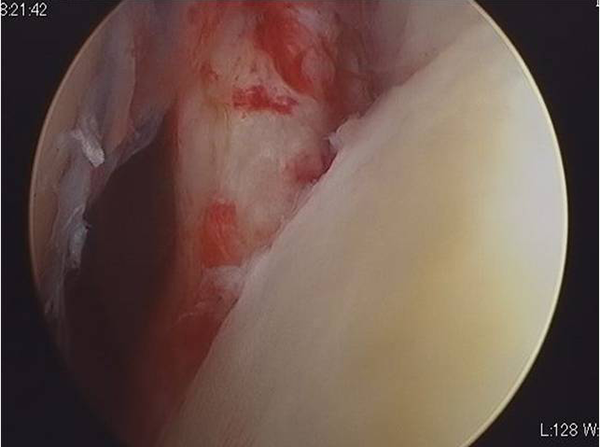

肩関節脱臼の関節鏡(カメラ)による手術では、脱臼によって剥がれ落ちた関節唇と呼ばれる組織(写真1)を元に位置に修復します(写真2)。